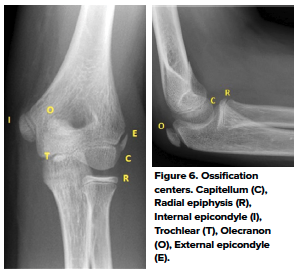

4. Identify ossification centers

There are 6 secondary ossification centers in the elbow. They ossify in a sex- and age-dependent predictable order. CRITOE is a mnemonic for the sequence of ossification center appearance. (Table 1 and Fig 6)

The medial epicondyle fuses to the shaft of the humerus at 13 years for females and 15 years for males. The growth plates are vulnerable to traction or shearing forces which result in fracture and/or apophyseal injuries. Displaced epicondyle fractures can be missed if the normal pattern of ossification development is not recognized.7